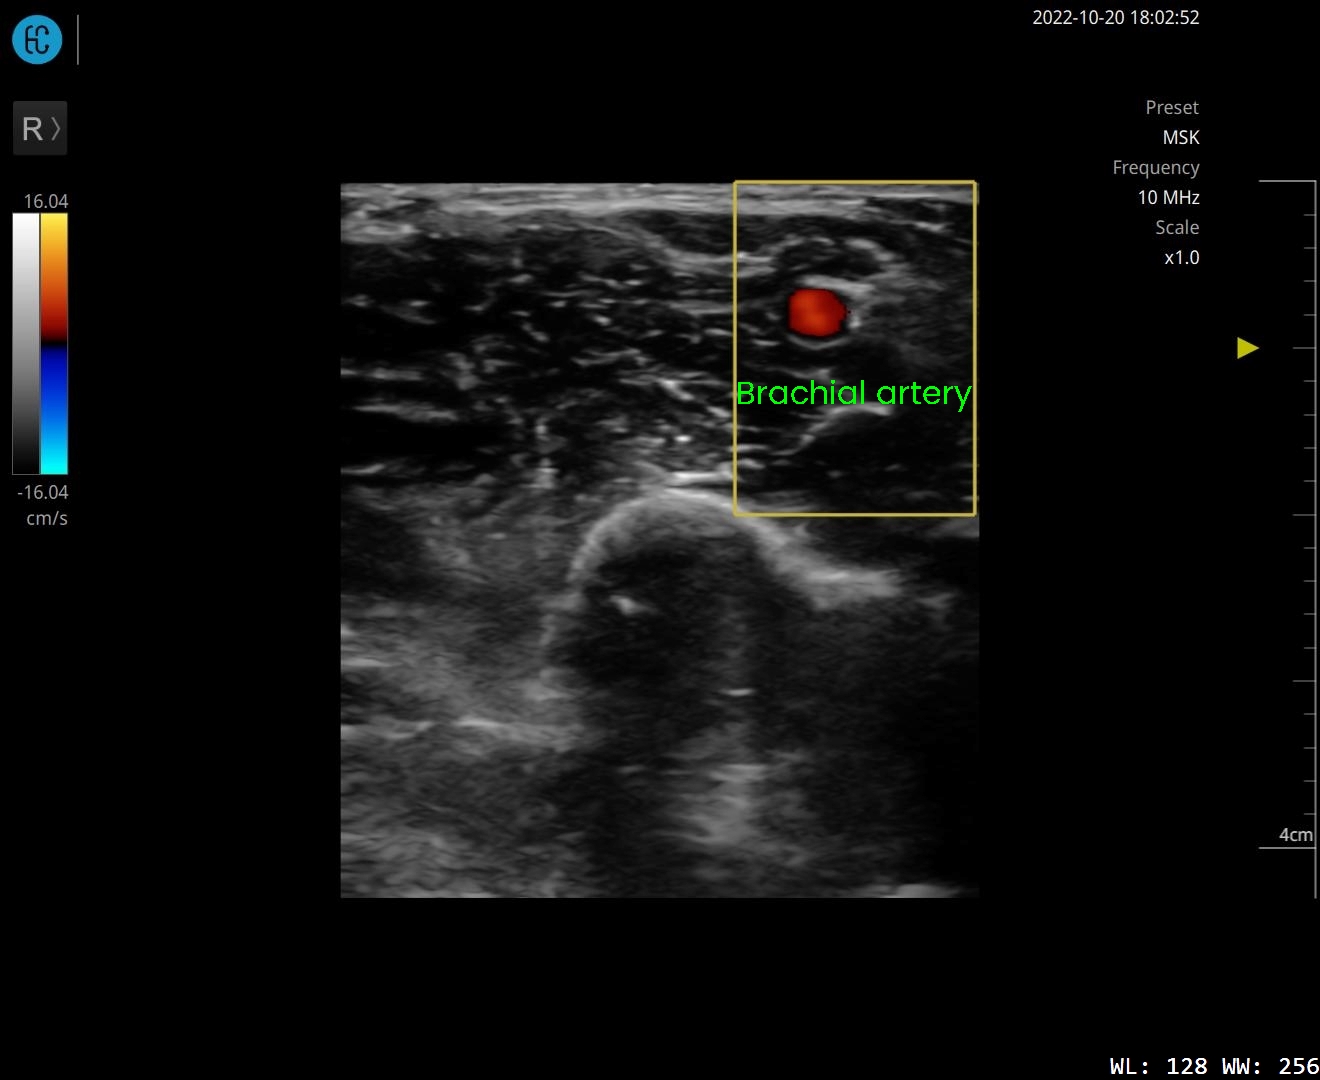

SONON 500L ecografía 1 SONON 500L ecografía 2 SONON 500L ecografía 3